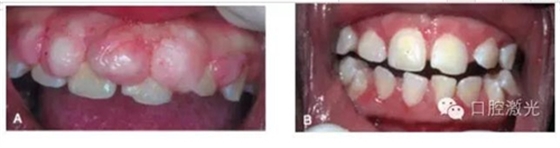

典型的激光口腔軟組織切除術當場效果

牙齦部分增生激光切除前及1周后效果對比